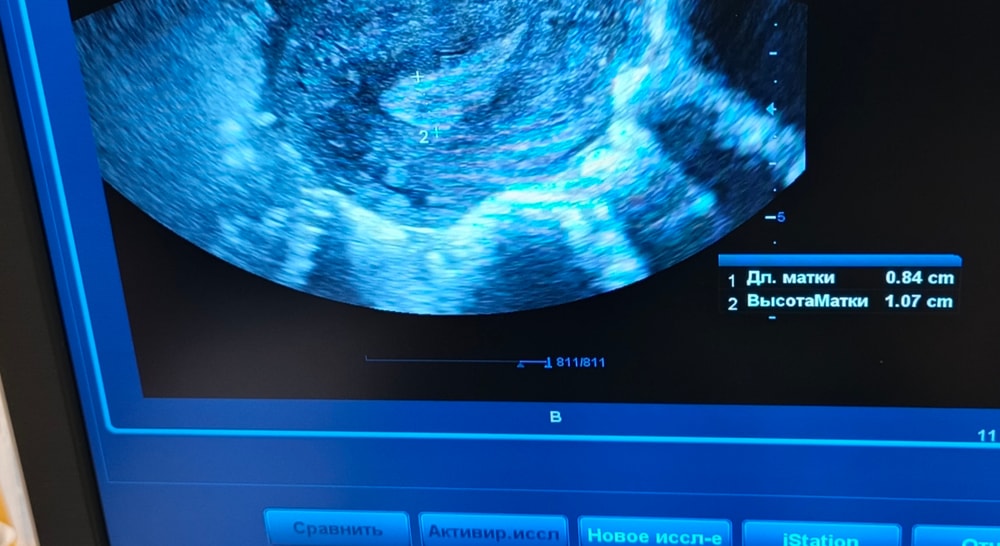

Все я устала ничего не хочу уже. 😔 Была опять сегодня на узи 🤦 Овуля поздняя была , жт какое то странное . Кистозное. Больше похоже на перерождение в кисту . Стенки как у медузы. Еще и сосечек какой то внутри хз страх да и только. По фоликам вообще молчу там даже смотреть нечего. Больше всего расстроил кровоток в эндометрии его как бы нет. ⛔ 🗿🥺 Эндик если до этого был 10мм в нижней трети в дне 6мм. То сейчас в дне 8,9-10 в нижней трети 6. Не знаю, я что делать. Препараты для кровотока пью. Физио прошла. От хэ пролечилась 💊. Эстрогены были прог ставила. Походу так до переноса я не дойду 🙄🥺.

Посмотрите снимки может есть какие мысли ?? 🤔 🙏